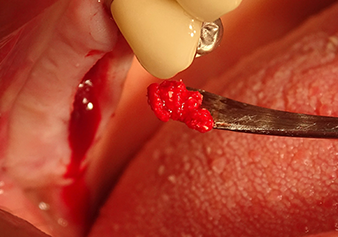

The I2A instrument (diameter 2.0 mm) was then used to perforate the sinus floor intermittently and on the smallest scale possible. This special piezosurgical method ensures that the Schneiderian membrane is not damaged. When the Z25P was used, the membrane was already lifted slightly by the coolant supplied via the instrument tip (Fig. 3). The coolant quantity was just 50% in order to avoid high pressure in the implant bed.